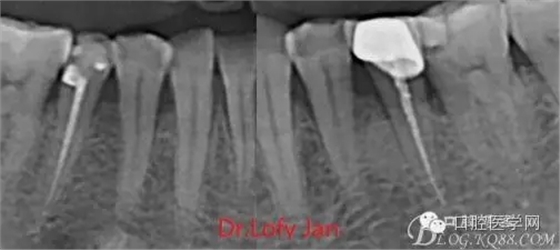

《數(shù)字化根尖片、曲面斷層片、CBCT測(cè)量牙齒長(zhǎng)度準(zhǔn)確性的比較研究》文中顯示:平行投照數(shù)字化根尖片影像長(zhǎng)度和牙齒實(shí)際長(zhǎng)度之間無顯著性差異(P0.05);數(shù)字化曲面斷層片影像長(zhǎng)度和牙齒實(shí)際長(zhǎng)度之間有顯著性差異(P0.05),平均失真率為17.05%。CBCT冠狀面測(cè)量結(jié)果中除上頜前磨牙區(qū)、下頜前磨牙區(qū)與真實(shí)長(zhǎng)度差異無統(tǒng)計(jì)學(xué)意義(P0.05)外,其余6個(gè)分區(qū)差異均有統(tǒng)計(jì)學(xué)意義(P0.05);矢狀面測(cè)量結(jié)果中上頜磨牙區(qū)、下頜磨牙區(qū)、下頜前磨牙區(qū)、下頜尖牙區(qū)、下頜前牙區(qū)與真實(shí)長(zhǎng)度比較差異均有統(tǒng)計(jì)學(xué)意義(P0.05)。結(jié)論平行投照數(shù)字化根尖片較曲面斷層片和CBCT能更加精確地反映牙齒的真實(shí)長(zhǎng)度。